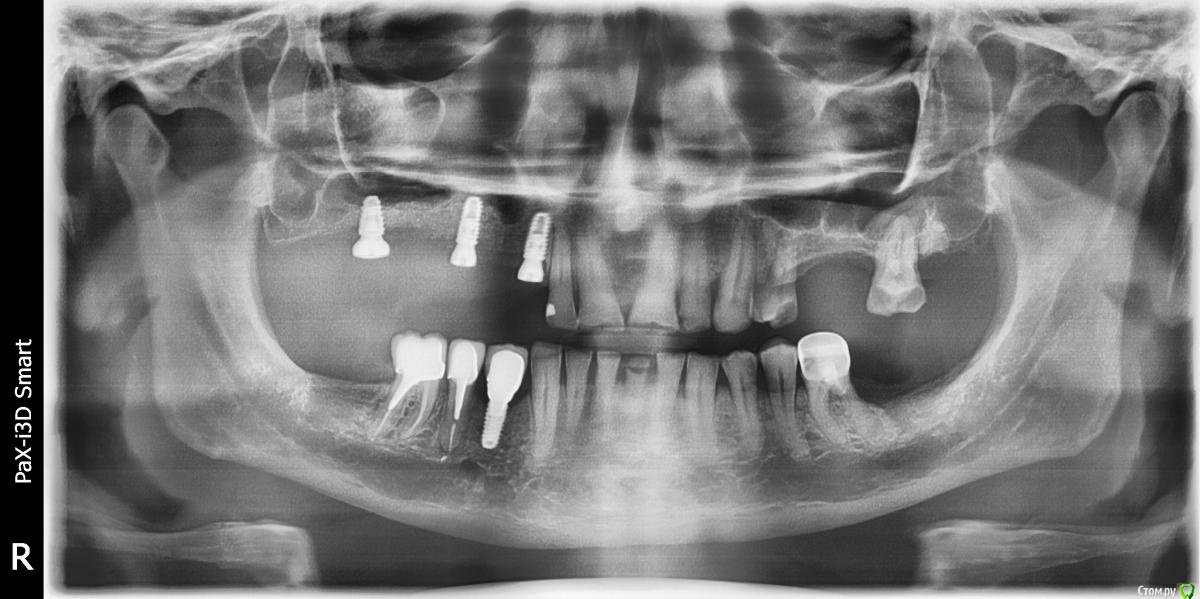

kamranchick Опубликовано 4 мая, 2018 Поделиться Опубликовано 4 мая, 2018 Обратился пациент после очередной халтуры которыми радуют меня коллеги из соседних клиник)фотопротокол ни как у Сашки Гудкова но более-менее понятно))Обратился пациент, в соседней клинике удаляли зуб, корень протолкнули в пазуху, далее пациент попал в ЧЛХ, там сделали радикальную гайморотомию, все достали, и вот попал пациент ко мне, так как в другой клинике сказали что у вас тут залу*а, а не кость, ну и погнали.1. пытался остро отслоиться, перфа на перфе, закрывал prf, мембранами, губками, стики бон + синус имплантация. ожидание 9 месяцев2. Пластика мягких тканей ожидание 2 месяца. 13 Ссылка на комментарий

Kazankov.Egor Опубликовано 5 мая, 2018 Поделиться Опубликовано 5 мая, 2018 Обратился пациент после очередной халтуры которыми радуют меня коллеги из соседних клиник)фотопротокол ни как у Сашки Гудкова но более-менее понятно))Обратился пациент, в соседней клинике удаляли зуб, корень протолкнули в пазуху, далее пациент попал в ЧЛХ, там сделали радикальную гайморотомию, все достали, и вот попал пациент ко мне, так как в другой клинике сказали что у вас тут залу*а, а не кость, ну и погнали.1. пытался остро отслоиться, перфа на перфе, закрывал prf, мембранами, губками, стики бон + синус имплантация. ожидание 9 месяцев2. Пластика мягких тканей ожидание 2 месяца.К кому сходить на мягкие ткани? Посоветуйте пожалуйста. Ссылка на комментарий

Eddie Опубликовано 7 мая, 2018 Поделиться Опубликовано 7 мая, 2018 У вас тут в области 13 и 15 диаметры имплантатов 3.5(3.8)? Выдержат такую конструкцию? Ссылка на комментарий

kamranchick Опубликовано 7 мая, 2018 Автор Поделиться Опубликовано 7 мая, 2018 У вас тут в области 13 и 15 диаметры имплантатов 3.5(3.8)? Выдержат такую конструкцию?ну да, а что ей будет) связанная конструкция, на израиле 3.75, служат) Ссылка на комментарий